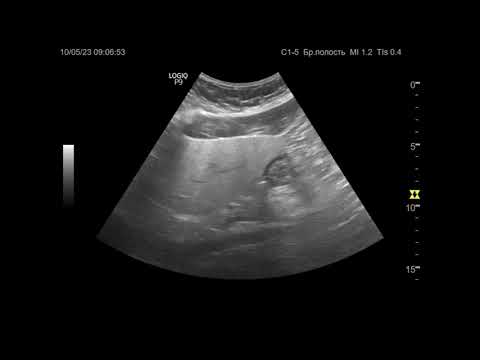

ГАСТРОЭНТЕРОЛОГИЯ. Видеозапись онлайн-семинара для врачей "Гепатомегалия: от симптома — к диагнозу" О семинаре: В ходе онлайн-семинара будут рассмотрены причины клинически значимого увеличения печени, а также — диагностические алгоритмы для уточнения нозологических форм при наличии этого симптома. Докладчик: Виктор Игоревич Немцов Профессор кафедры госпитальной терапии ПСПбГМУ им. акад. И.П. Павлова, доктор медицинских наук, профессор Дата проведения: 27.02.24 в 20:00 мск Организатор: Образовательный центр Фармамед.РФ - один из крупнейших образовательных порталов в России. Бесплатные онлайн-семинары в программе НМО. Ссылка на видео:    • Профессор Немцов В.И.: Гепатомегалия: от с...   Читайте актуальные новости медицины: